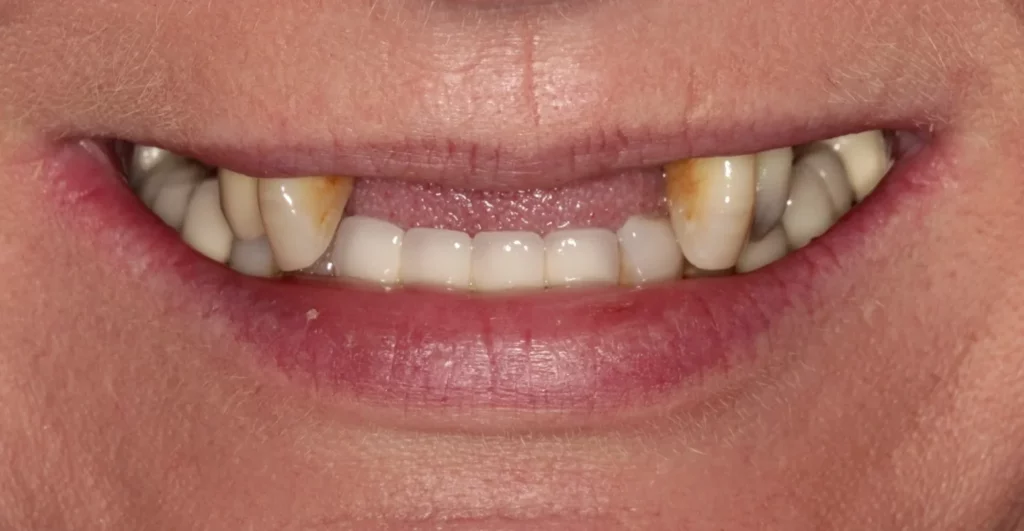

This lady was embarrassed by her yellow teeth and the gaps. The remaining upper teeth were loose from smoking-related gum disease. The upper front teeth were removed, and a temporary denture was placed to allow healing so that the implants could go into a clean bone environment with higher chances of treatment success. A few months later, six upper implants with bone grafting were placed and then a strong porcelain bridge with 12 teeth was fitted on top of the implants.

This patient was fed up with her denture and remaining loose upper teeth.

5 upper implants have been placed that support a bridge with 13 teeth in the top jaw.

This is a full arch porcelain bridge which the lady was delighted with.